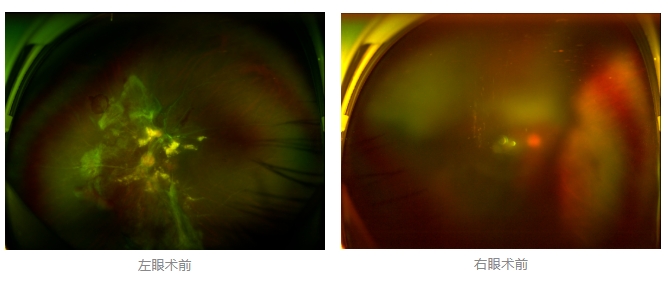

經(jīng)廈門眼科中心眼底病專科行政主任王曉波檢查后,確診其雙眼糖尿病視網(wǎng)膜病變VI期,伴發(fā)雙眼視網(wǎng)膜脫離和黃斑水腫,且右眼視網(wǎng)膜上增殖膜叢生,若再不盡快進(jìn)行治療,恐有失明風(fēng)險(xiǎn)。

面對(duì)陳先生的復(fù)雜病情,王曉波主任采用玻璃體切割術(shù)聯(lián)合膜切除術(shù)等方式,精細(xì)剝離牽拉視網(wǎng)膜的增殖膜,復(fù)位脫離的視網(wǎng)膜,同時(shí)進(jìn)行玻璃體腔注藥促進(jìn)黃斑水腫吸收。

經(jīng)過(guò)規(guī)范化治療,術(shù)后2個(gè)月復(fù)查時(shí)陳先生的視力已有明顯改善,矯正視力從眼前指數(shù)提升至0.3,成功擺脫“失明危機(jī)”。但王曉波主任強(qiáng)調(diào):“這只是階段性勝利,后續(xù)治療不能松懈。”